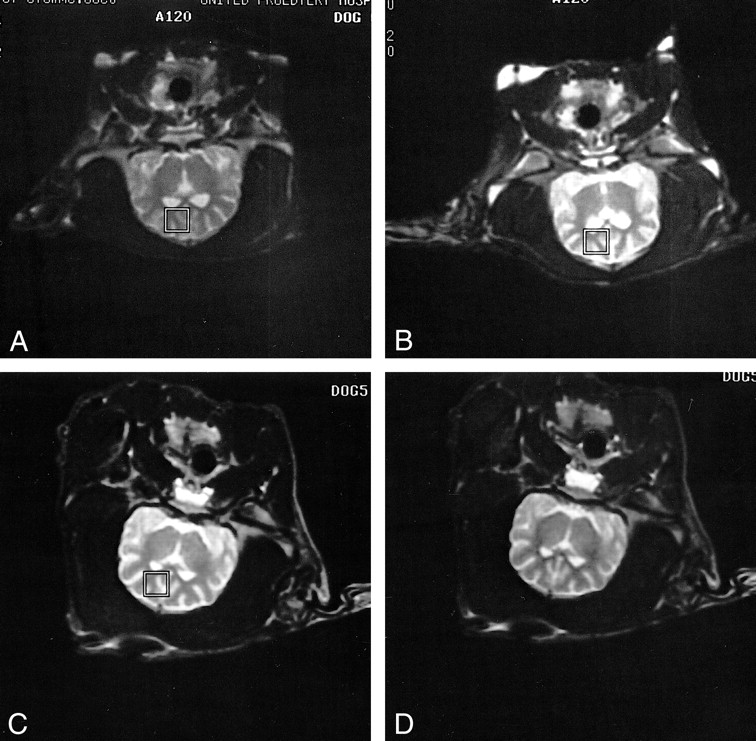

Five adult mongrel dogs (three male, two female; 15–25 kg) were sedated with intramuscular fentanyl, droperidol, and atropine, and infused with thiopental (15–25 mg/kg IV). They were anesthetized with intravenous fentanyl and droperidol (0.4 mg fentanyl plus 20 mg droperidol/mL infused at 0.1 mL/kg per hour) (22). The anesthetic infusion was titrated with additional intravenous and intramuscular administrations of fentanyl, droperidol, and atropine as needed. The animals were intubated for airway protection and mechanically ventilated with supplemental oxygen. The neuromuscular blocking agent pancuronium (0.08 mg/kg IV Q 60–90 minutes) (23) was administered as needed throughout both the control and stimulus experiments to eliminate subject motion (Fig 1). Oxygen delivery and ventilation rates were adjusted to maintain heart rate, blood oxygen saturation (SPO2), and blood pH within normal limits. Heart rate and SPO2 were continuously monitored with MR-compatible equipment (Invivo Research, Inc, Orlando, FL). Arterial blood pH and glucose levels (glucometer; Lifescan, Inc, Ft Washington, PA) were sampled periodically.

A and B, T2-weighted fast spin-echo localizer images show reproducible locations for single-voxel proton MR spectra obtained in the same subject in control (A) and postictal (B) experiments conducted on different days.

C and D, T2-weighted fast spin-echo localizer images in another subject before (C) and 3 hours after (D) PTZ-induced generalized seizures show no evidence of head movement or cerebral edema at the conclusion of a postictal experiment.

Multiple T2-weighted coronal MR images were acquired to localize a single cubic voxel (10.3 × 10.3 × 15 mm) for subsequent spectroscopic acquisition. The voxel was centered in the left frontal lobe cortex, in which scalp fat was avoided and CSF minimized by inspection of localizer images (Fig 1). MRS voxels were placed over the same area of the frontal lobe cortex in both control and stimulus experiments as determined by localizer images. Parameters for spectroscopic acquisition were as follows (24): a point-resolved spectroscopy (PRESS) excitation sequence using two-cycle phase alteration and three chemical shift-selective (CHESS) pulses for water suppression (bandwidth 50 Hz), a TR/TE of 1500/41, an acquisition bandwidth of 1000 Hz, and a 1024-point data array. A total of 256 images were averaged for an acquisition time of 6.4 minutes. Before the acquisition of the solvent-suppressed metabolite data, a spectrum of unsuppressed water was obtained under identical parameters for use as phase and concentration references during postprocessing.